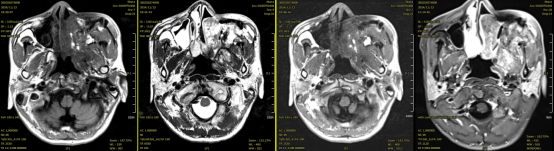

Efficacy Evaluation: The patient has completed carbon ion therapy. A follow-up MRI of the sinuses and neck showed that the multiple irregular nodules and masses in the left nasal cavity, left maxillofacial region, periorbital area, and nasal root have significantly reduced in size compared to before treatment. The tumor response is evaluated as Partial Response (PR).

Figure 4: Before treatment: Multiple irregular nodules and masses were observed in the left nasal cavity, nasopharynx, oropharynx, left maxillofacial region, periorbital area, and nasal root, with extensive invasion of the left parapharyngeal and maxillofacial muscles.

Figure 5: After treatment: Multiple irregular nodules and masses in the left nasal cavity, left maxillofacial region, periorbital area, and nasal root, with localized invasion of the left parapharyngeal and maxillofacial muscles, have shown a reduction in size compared to previous imaging.